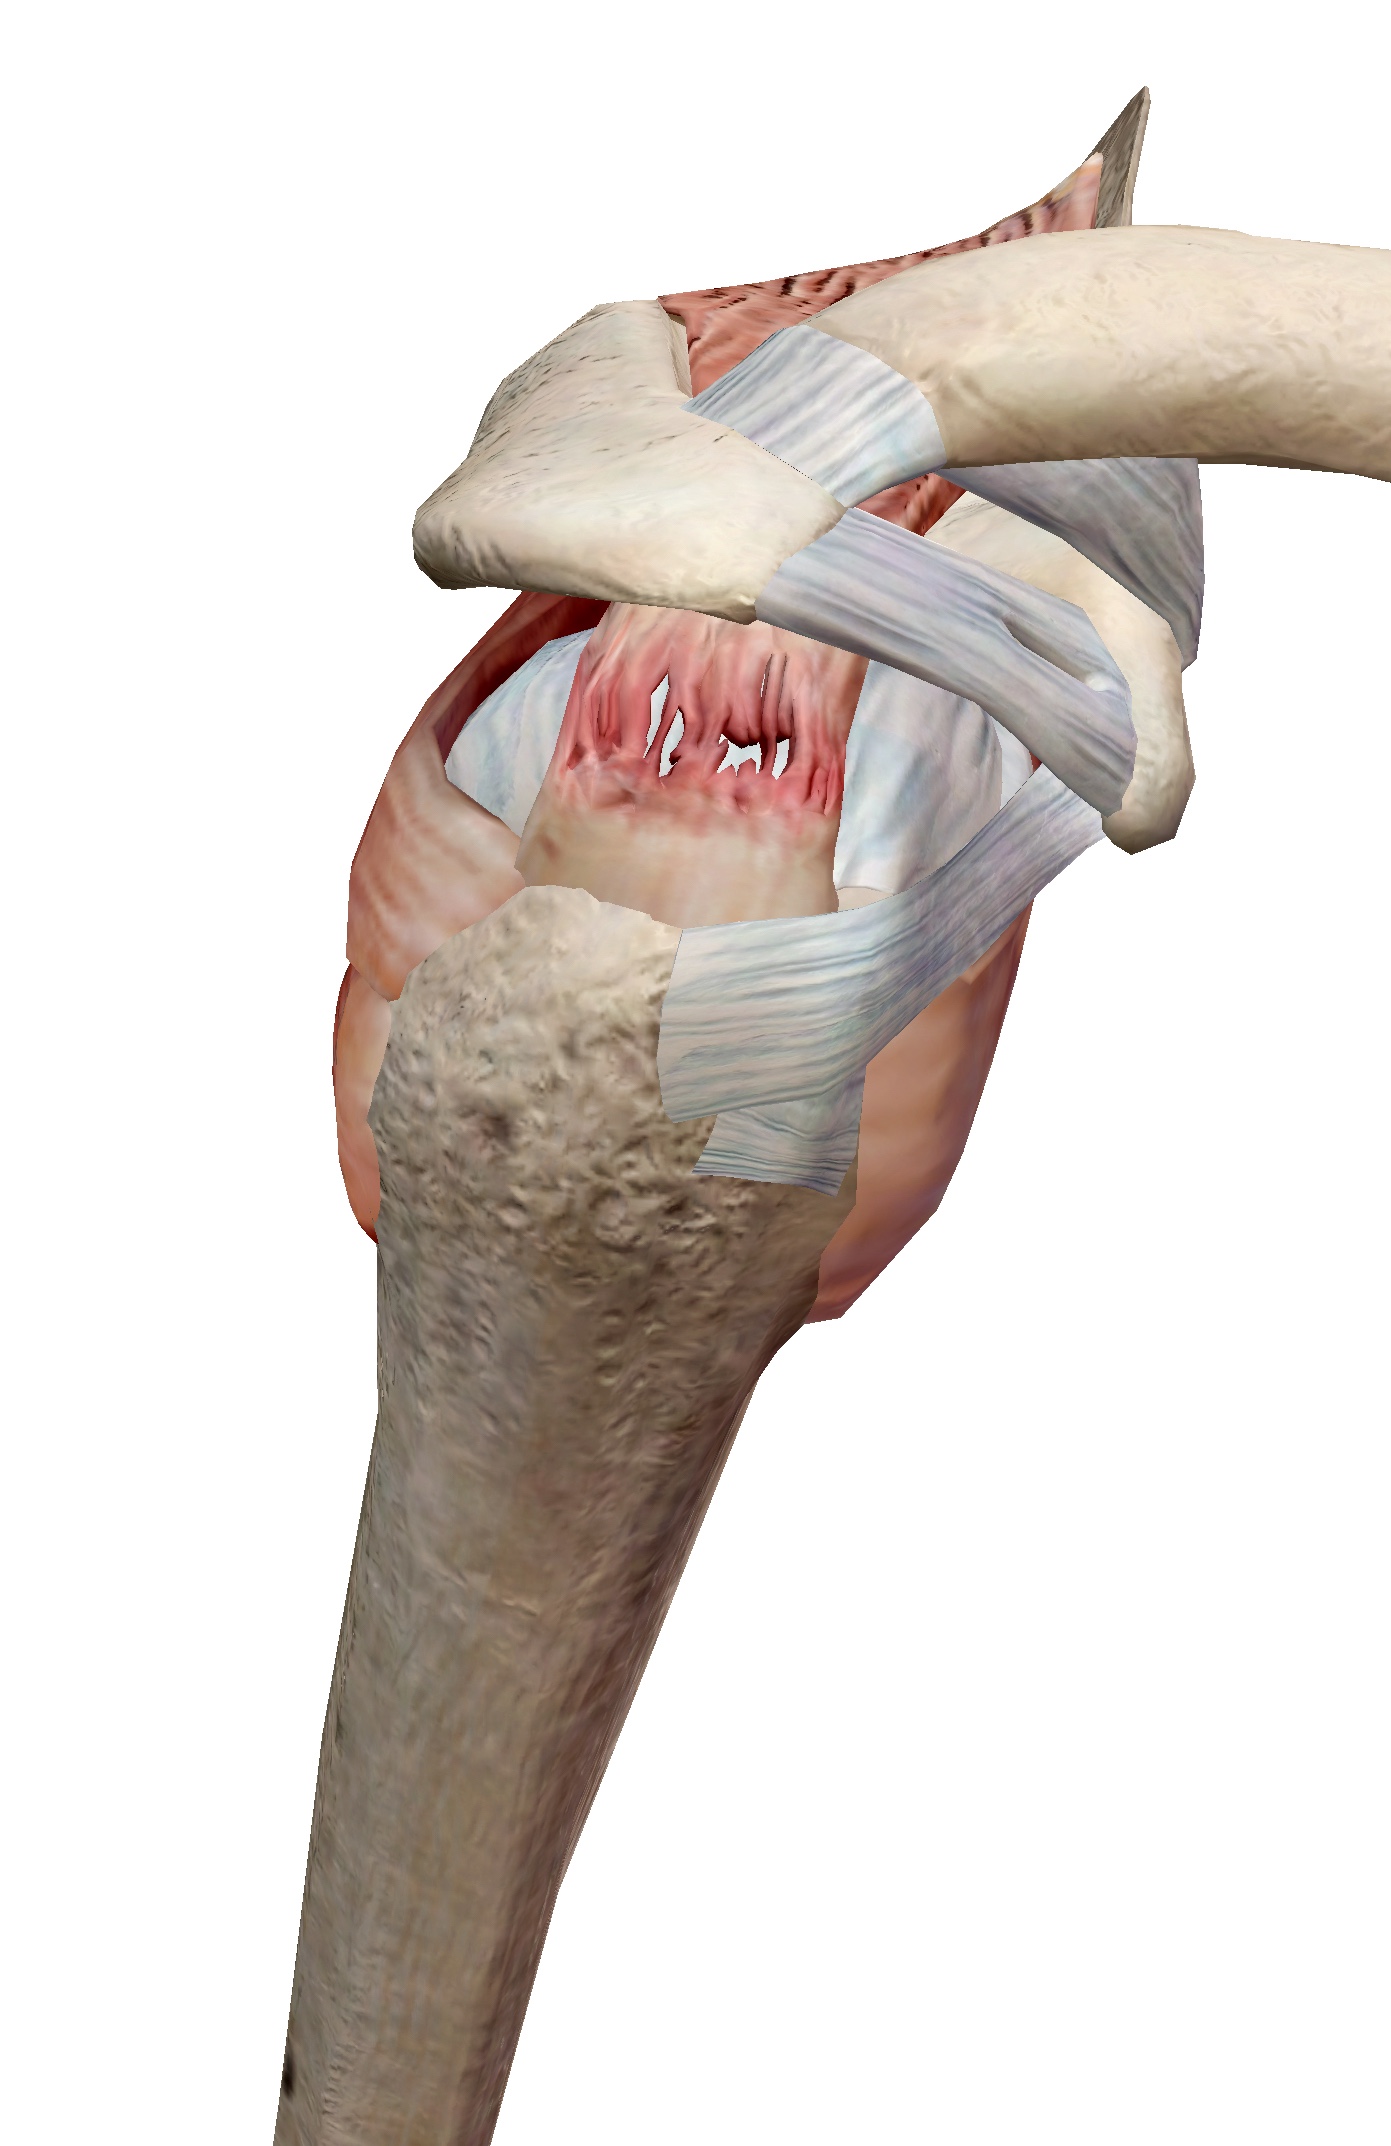

2. แขนไม่มีแรงหรือยกแขนไม่ขึ้น

หากคุณพบว่าแขนไม่มีแรง ยกแขนไม่ขึ้น หรือรู้สึกว่าแขนทำงานไม่เต็มที่ อาจเกิดจากการ กล้ามเนื้อเอ็นไหล่ฉีกขาด หรือ เส้นประสาทถูกกดทับ ซึ่งถ้าไม่รับการรักษาทันท่วงที อาการอาจแย่ลงและส่งผลกระทบต่อการใช้งานไหล่ในระยะยาว